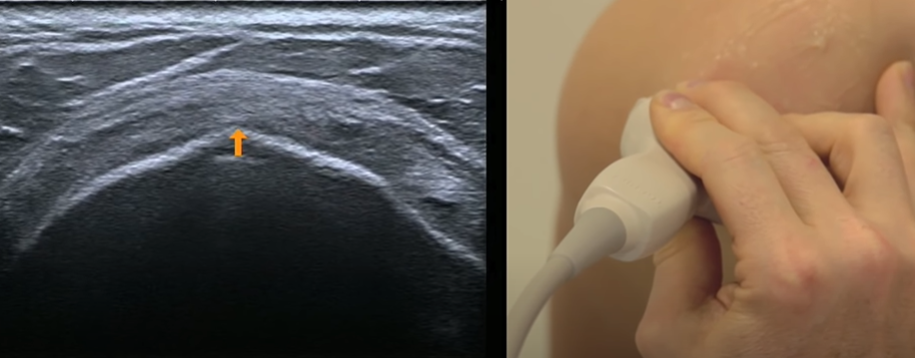

Sub-scapulaire

- Rotation externe de l’épaule, plaquée au corps

- S’insère sur le tubercule mineur

- Quelques fibres maintiennent le long biceps

- Identifier le processus coracoide

- Coupe axiale

- Manoeuvres dynamiques en axial (ouvrir et fermer l’épaule, regarder le comportement du tendon sous le coracoide

- Coupe longitudinale: on voit bien les espaces hypoechogènes entre les faisceaux du tendon

Coupe longitudinale

Manoeuvres dynamiques rotation

Coupe axiale avec les fasiceaux